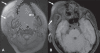

Congenital infiltrating lipomatosis of the face is a rare condition characterized by diffuse fatty infiltration of the facial soft tissues. There may be muscle involvement along with associated bony hyperplasia. It is a type of lipomatous tumor that is congenital in origin; it is rare and seen usually in childhood. We recently saw an 11-year-old girl with this condition. She presented with a swelling of the right side of the face that had been present since birth; there were typical findings on plain radiographs, CT, and MRI. The patient underwent cosmetic surgery. Histopathological examination showed mature adipocytes without any capsule.